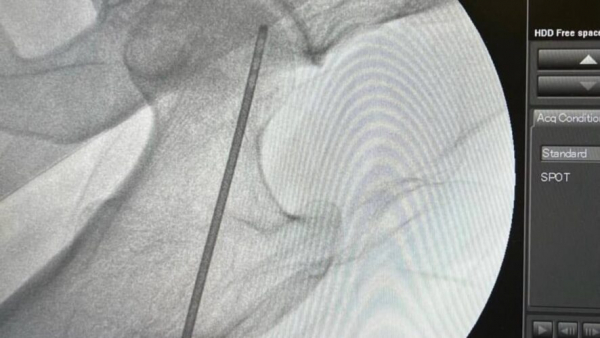

Заведующий отделением травматологии №1 Гамиль Гарифуллов предложил методику, которая даёт возможность отсрочить замену суставов. Травматологи просверлили канал до очага некроза и ввели в него стволовые клетки. Перед операцией травматологи забирают жировую ткань с передней брюшной стенки, центрифугируют и поучают стромально-васкулярные клетки. Смешивают их с плазмой пациента и этот «коктейль» вводят в очаг некроза.